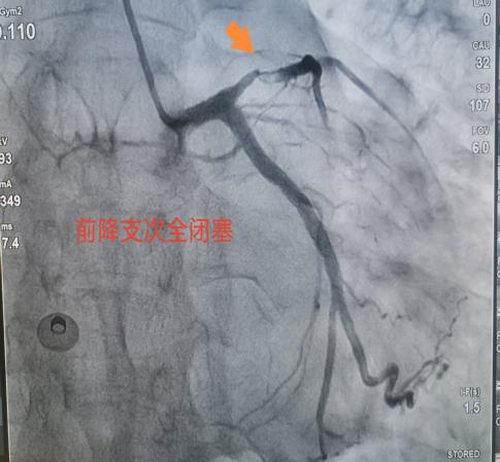

据悉,该患者因粗大前降支近段闭塞,遭受严重胸痛折磨。在接受急诊手术过程中,情况急转直下,患者突然意识丧失,心电监测显示室颤——这是一种极其危险的心律失常,如不及时处理,患者生命将在短时间内消逝。面对这一危急情况,心血管病科团队迅速反应,立即启动电除颤抢救。医护人员争分夺秒,精准操作,与死神展开了一场惊心动魄的较量。紧接着,团队成员凭借丰富的临床经验和高超的介入技术,快速完成导丝通过及支架植入,成功实现血管再通。手术的每一个环节都紧密衔接,每一个操作都精准无误,为患者的生命赢得了宝贵的时间。术后,患者逐渐苏醒,他心有余悸地感慨:“仿佛经历了一次生死轮回。”目前,患者康复状况良好,为表达对心血管病科团队的感激之情,患者特意送来一面锦旗。